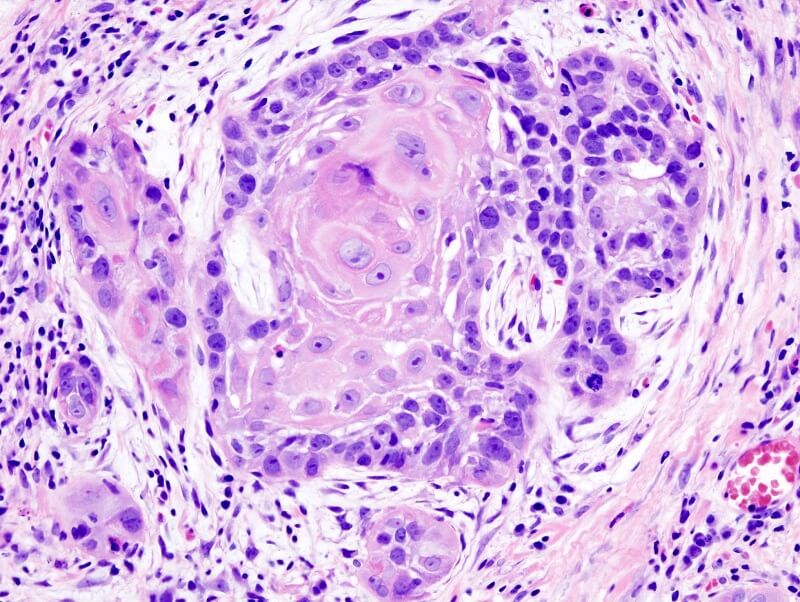

Giải phẫu bệnh được định nghĩa là chuyên ngành thuộc y học, nó có liên quan tới nghiệp vụ chẩn đoán bệnh lý thông qua việc dùng kính hiển vi để phân tích mẫu tế bào và mô trong cơ thể, từ đó giúp y bác sĩ chẩn đoán bệnh chuẩn xác hơn và xây dựng phác đồ điều trị hiệu quả hơn. Kết quả thu được từ quá trình phân tích sẽ được nêu trong báo cáo về giải phẫu.

Trong nghiệp vụ giải phẫu bệnh, người ta sẽ kiểm tra mô cơ thông qua sự kết hợp giữa mắt thường quan sát và kính hiển vi để soi tế bào rõ hơn gấp hàng ngàn lần. Hiện nay giải phẫu bệnh cũng ứng dụng phương pháp mới đó là chẩn đoán phân tử. Khi đó có sự liên quan tới vấn đề phân tích DNA và protein ở bên trong mô và máu. Rất nhiều lợi ích được đem tới nhờ phương pháp phân tích mới.

Giải phẫu bệnh là môn bệnh học, một môn học chuyên nghiên cứu tổn thương của mô, tế bào cũng như cơ quan bên trong cơ thể để phát hiện các trạng thái bệnh lý khác nhau.

Những tổn thương có thể quan sát được theo cách thông thường thì gọi là tổn thương đại thể. Còn những tổn thương của tế bào, của các mô chỉ nhìn nhận được khi soi dưới kính hiển vi với sự phóng đại càng ngàn lần sẽ được gọi là tổn thương vi thể, siêu vi thể.